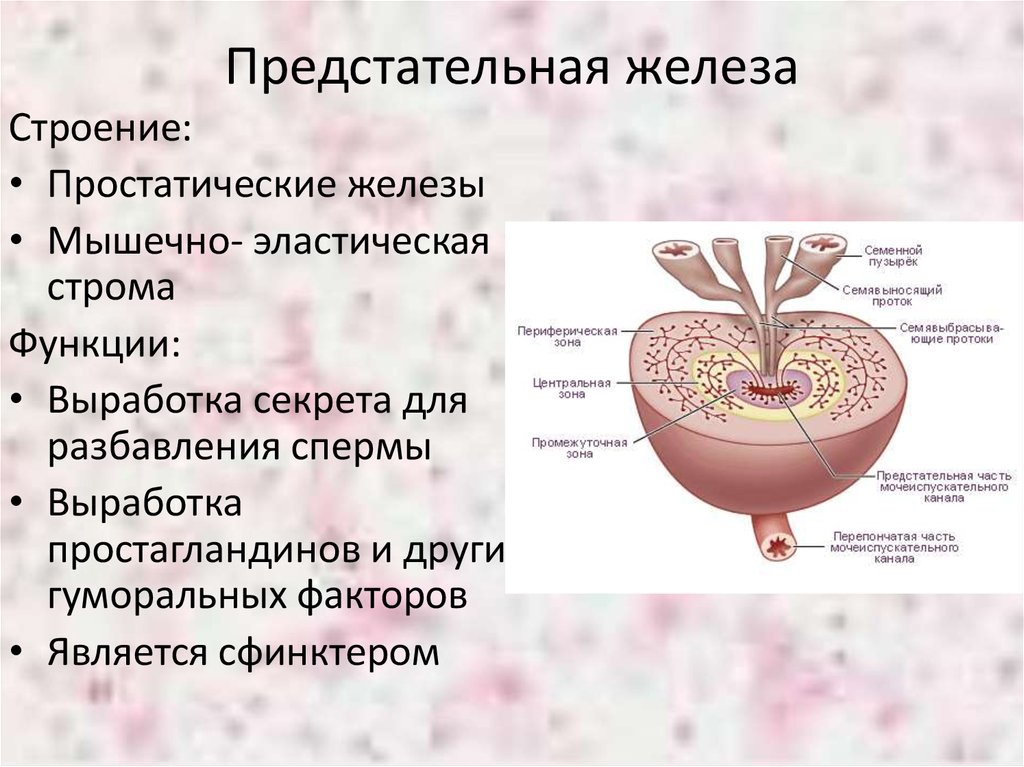

Простата, обычно ассоциируемая с мужским здоровьем после полового созревания, также присутствует у детей, хотя и в значительно меньших размерах. Этот орган, расположенный под мочевым пузырем и окружающий уретру, играет роль в выработке жидкости, которая составляет часть семенной жидкости. Несмотря на то, что проблемы с простатой у детей встречаются редко, понимание её развития и потенциальных патологий важно для ранней диагностики и лечения.